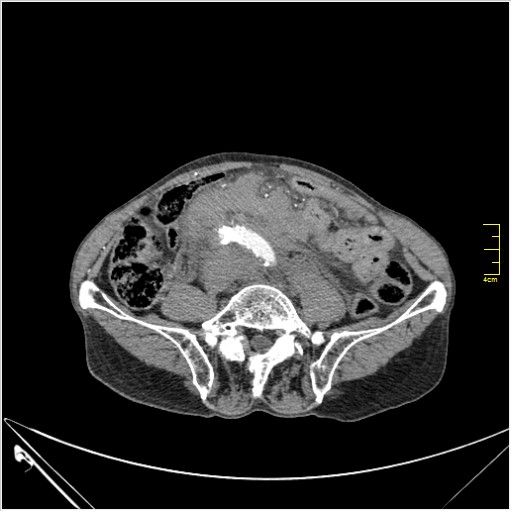

Пациент Т. 64 года, обратился на КТ брюшной полости амбулаторно (!), по направлению семейного врача с диагнозом abdominal mass, буквально: образование брюшной полости.

Huge abdominal aorta aneurism. Simple renal cortical cysts (Bosniak type 1).